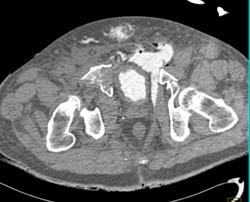

Diagnosis

Medial Sternotomy Without Complications